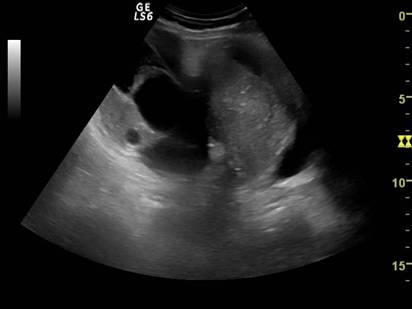

Fig, nr.380. Nodul fibromatos intramural si subseros al peretelui anterior uterin, in sectiunea sagitala a ecografiei abdominale